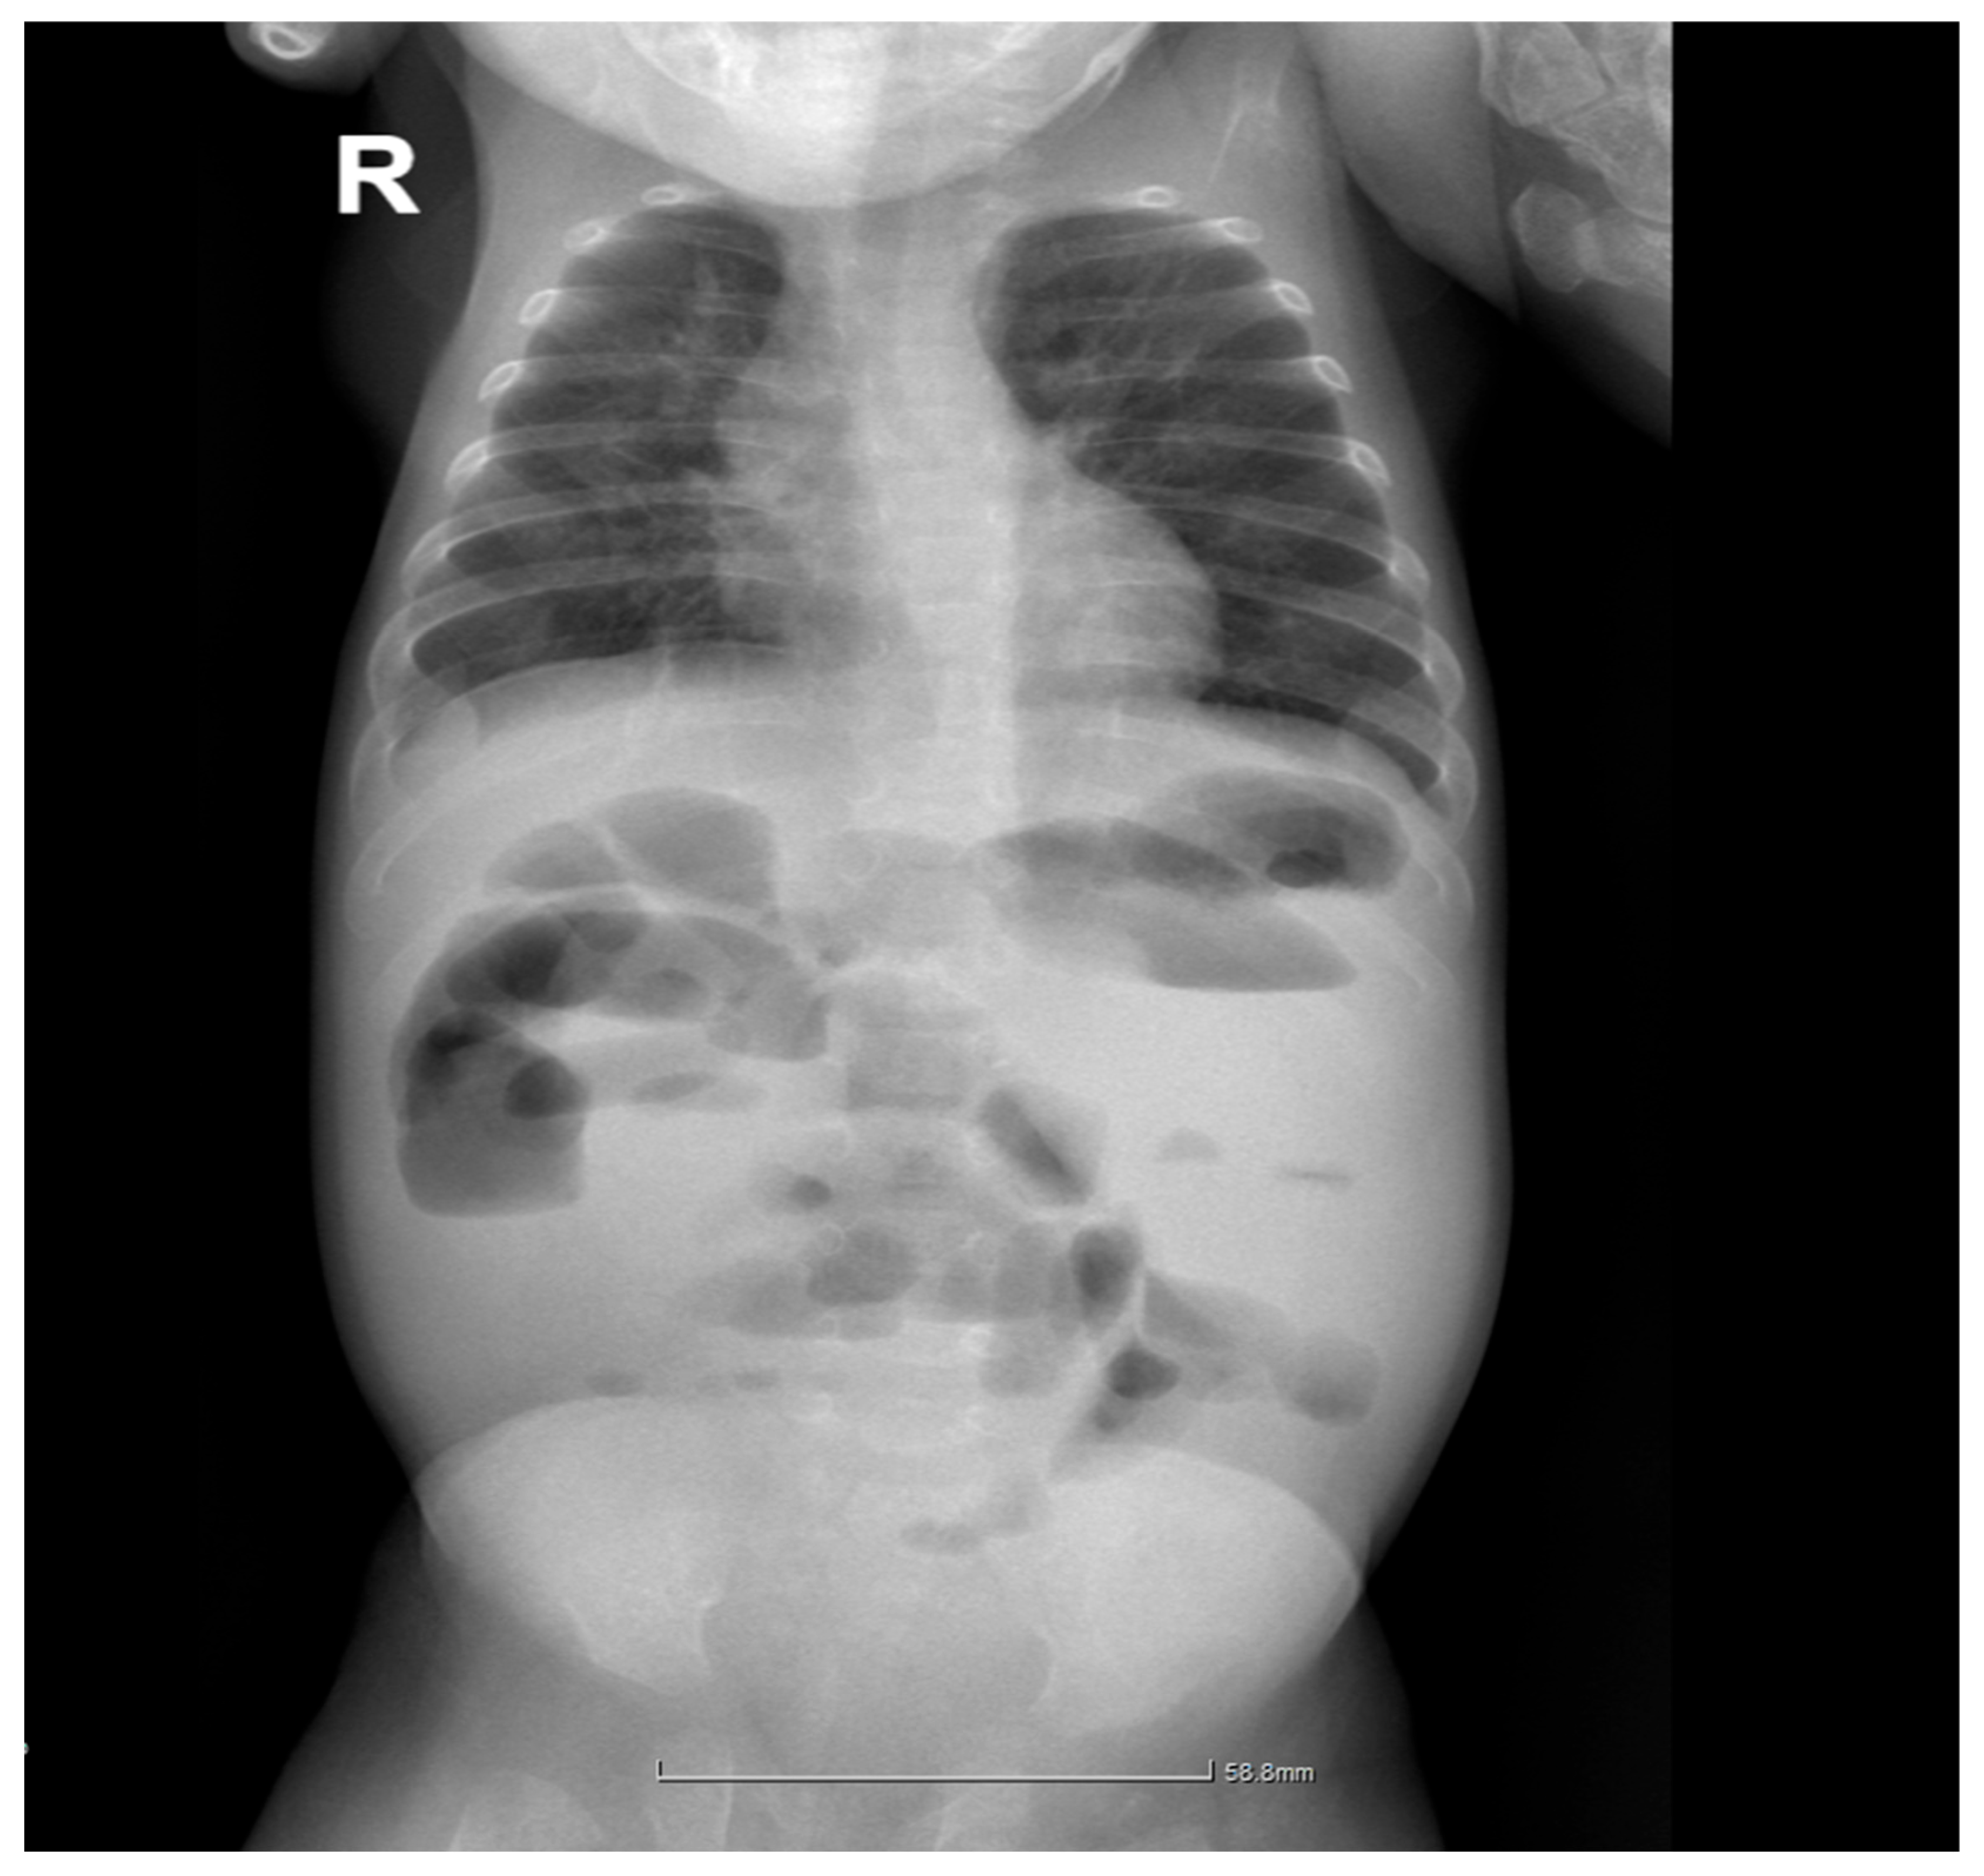

2.4. Gastrointestinal Complications and Diagnosis

2.5. Postoperative Course and Complications

| Day 12 | Intestinal obstruction suspected | Surgical consultation |